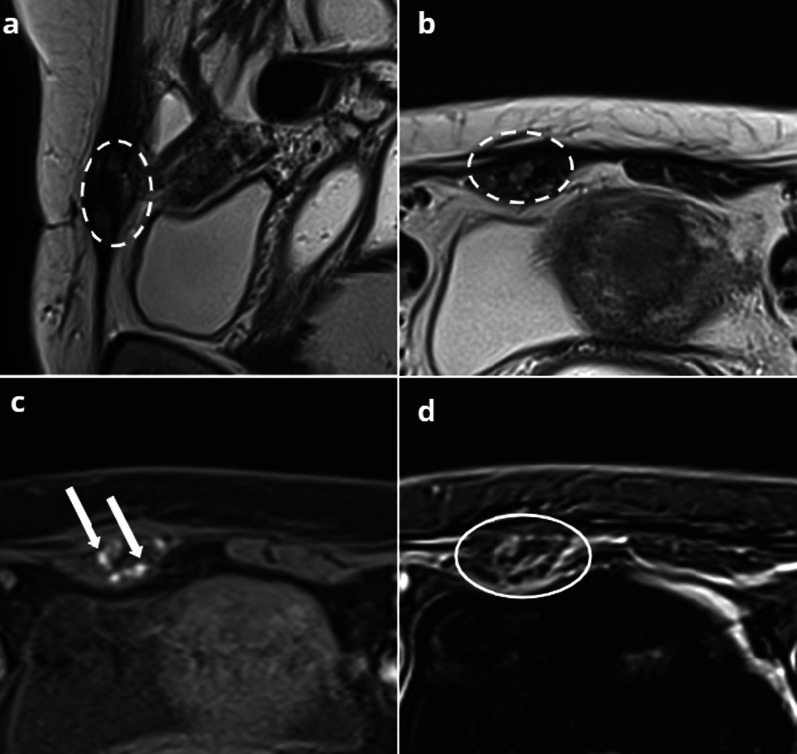

Fig. 9.

48-year-old female, with a history of severe endometriosis treated by surgery, presenting with hypogastric pain, elevated C-reactive protein (CRP) and white blood cell count. Axial T2W sequence (a) shows a complex cystic mass of the bladder wall (circle). b No hemorrhagic signal is observed on axial T1FSW sequence (arrows). After injection, axial T1FSW (c) depicts perivesical fat stranding and enhancement consistent with an inflammatory process (circle). Infected bladder endometriosis was suspected given the patient’s history, and a follow-up MRI was performed after antibiotherapy. Axial T2W sequence after treatment (d) shows a decrease in size of the mass. e Hyperintense spots appear on T1W FS sequences (arrows), and (f) inflammatory signs decrease after injection (dotted circle), consistent with the resolution of an infectious process involving the endometriotic mass